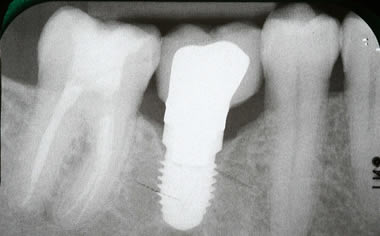

More back teeth replaced by dental implants

Case Three (2 images)

Case Four (4 images)

Case Five (4 images)